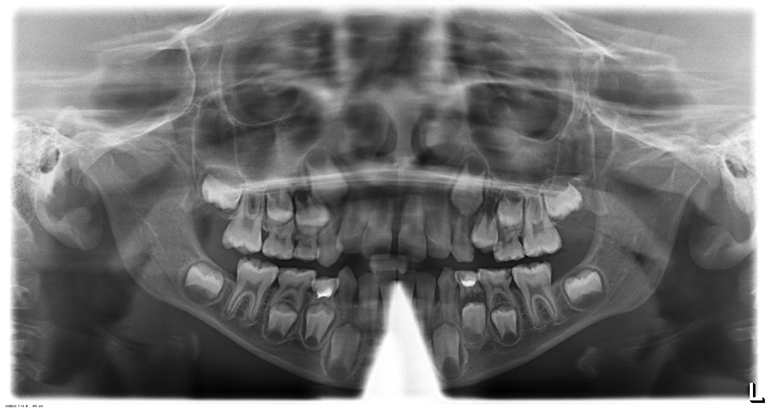

Добрый день. Алина Владимировна у нас есть снимок и там сказали, что воспаление под зубом. Надо удалять. Так ли это?

Нижний слева 4ый молочный зуб нужно удалить. 5ый нижний слева молочный зуб- лечить